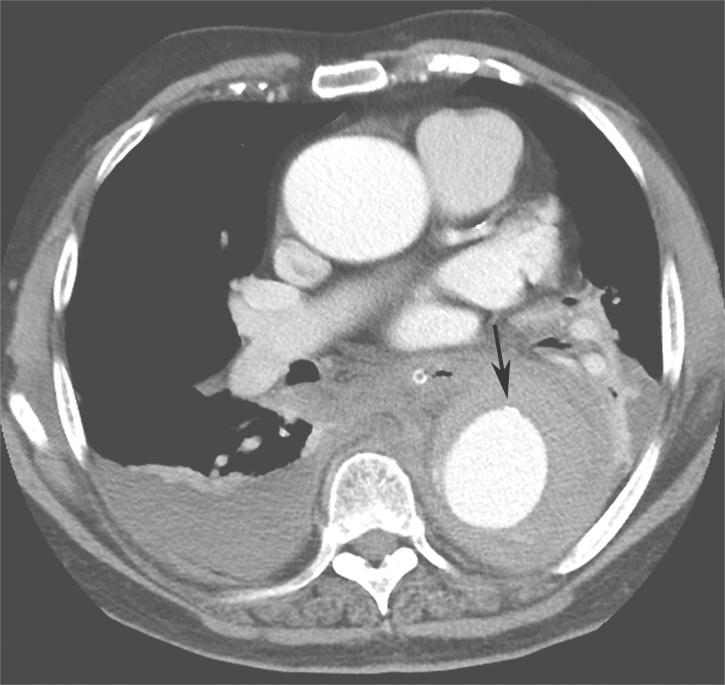

4.肺CT平扫

降主动脉瘤样扩张,直径较前有所增加,可见内膜移位,不除外主动脉夹层(图1)。

图1肺部CT平扫(箭头处钙化点内移)

3.患者既往存在升主动脉瘤样扩张病史多年,此次复查肺CT显示升主动脉直径较前有所扩大。症状上呈撕裂样疼痛,加之D-二聚体显著升高,考虑患者主动脉夹层的诊断可能性大。

对于急性胸痛的患者,2010年AHA指南中提出疑诊主动脉夹层(aortic dissection,AD)的高危易感因素、胸痛特征和体征(表1)。IRAD研究基于上述高危因素提出AD危险评分,根据患者符合危险因素分类(高危易感因素、高危疼痛特征及高危体征)的类别数计0~3分(0分为低危,1分为中危,≥2分为高危);该评分≥1分,诊断AD的敏感度达95.7%。因此,对存在上述高危病史、症状及体征的初诊患者,应考虑AD可能并安排合理的辅助检查以明确诊断。基于患者入院时病史询问、体格检查对疾病确诊极为重要。本例患者既往有升主动脉瘤样扩张及高血压病史多年,因突发胸痛入院,AD危险评分≥2分,为AD高危,且门诊胸部CT平扫可见降主动脉瘤样扩张,直径较前有所增加,可见内膜移位,高度怀疑主动脉夹层。